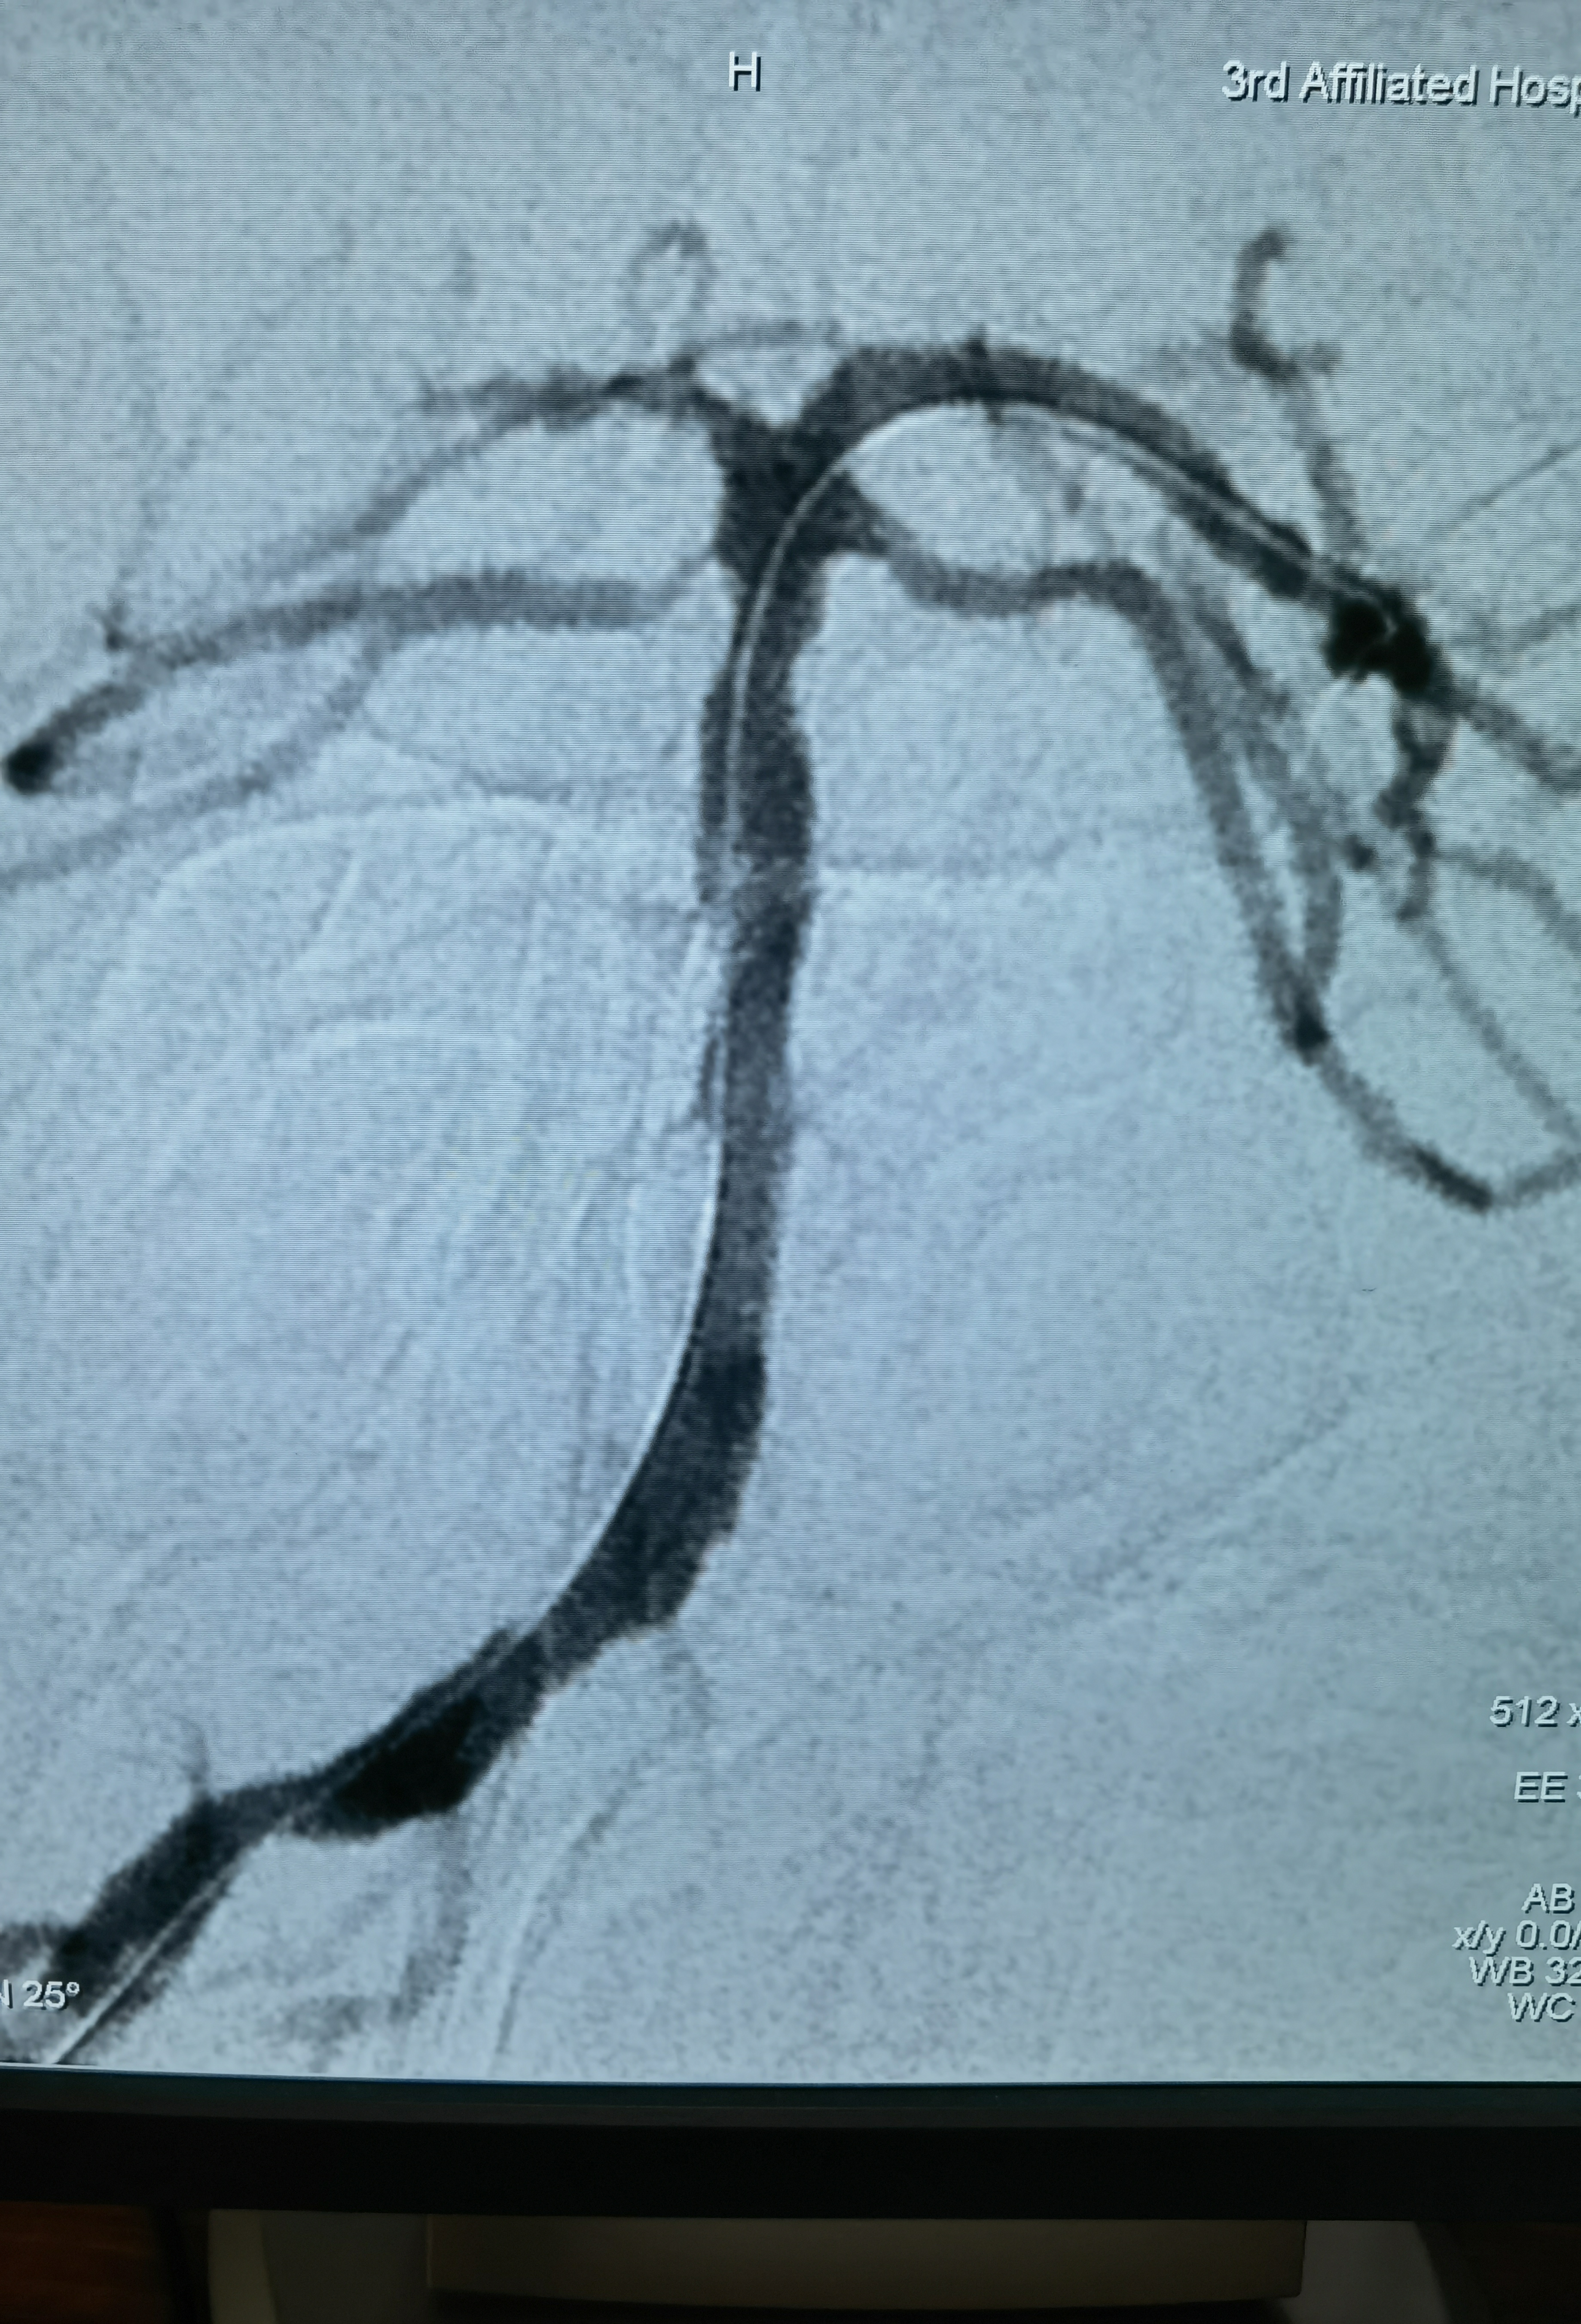

Gateway2.5*15压力打至8atm

扩张后造影

释放3.5*17Lvis支架

释放支架后造影